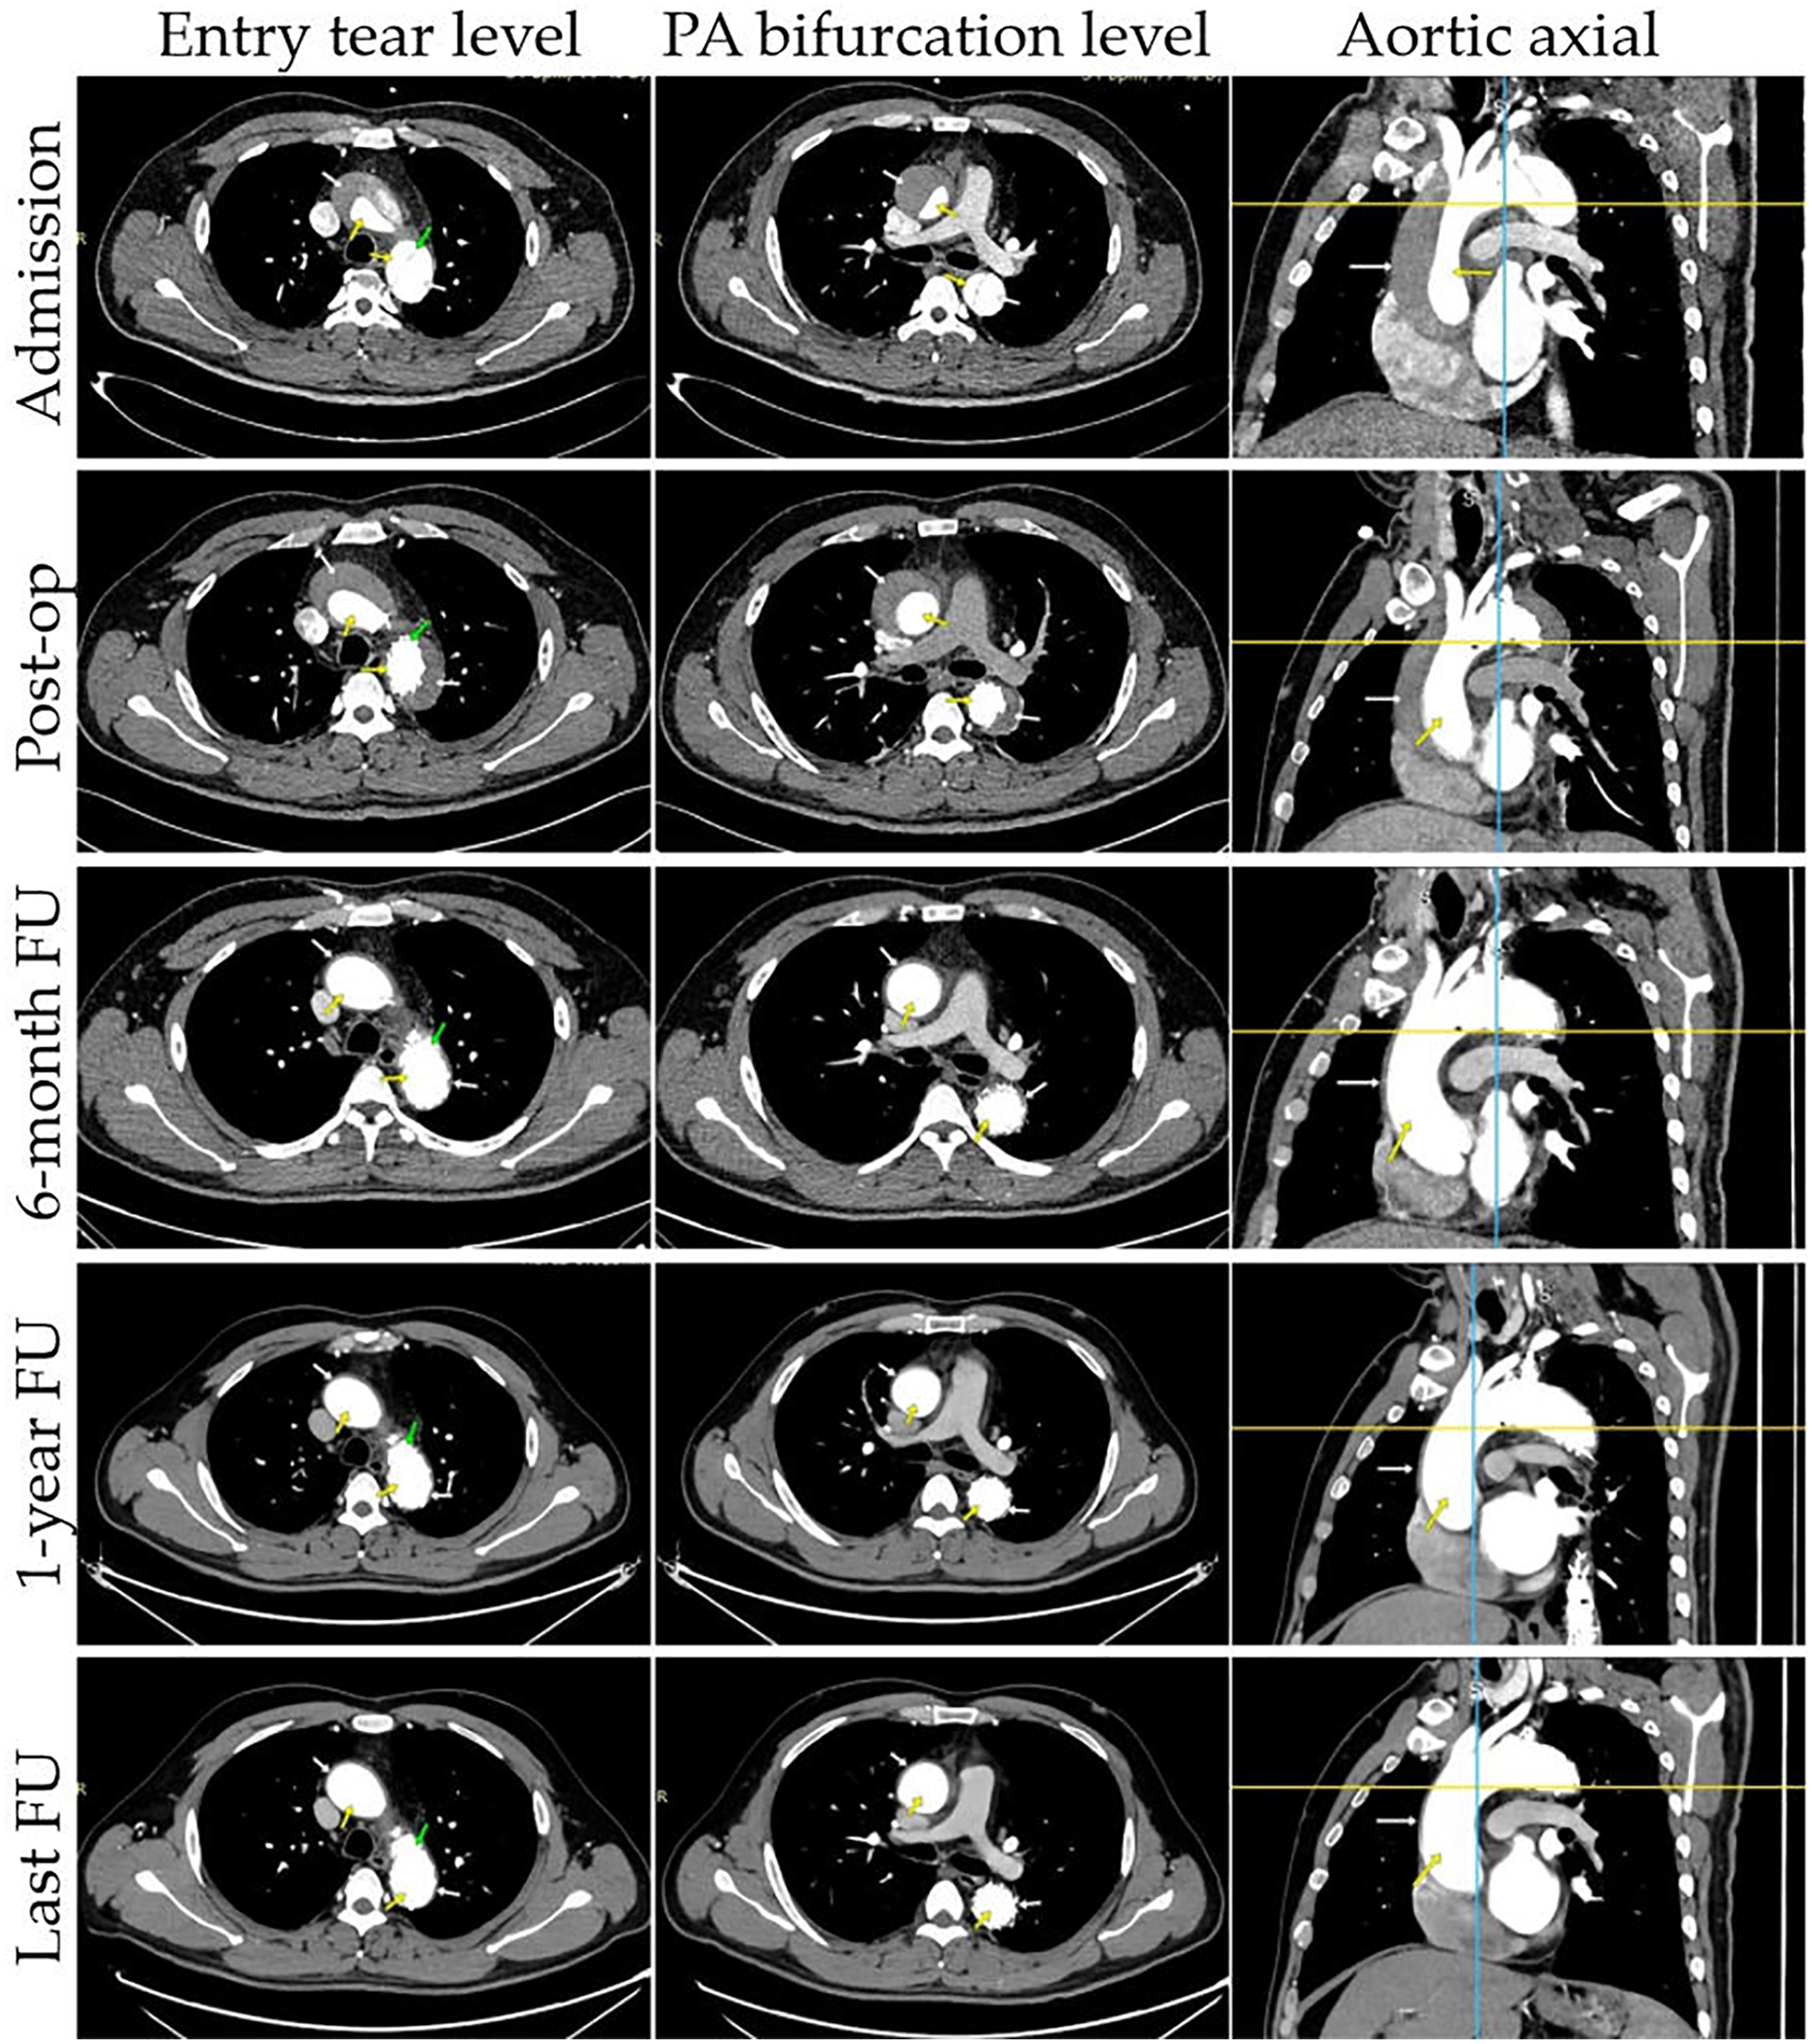

Figure 2

Representative cases of true and false lumens in different aortic segments. Results of CTA images at different time points are presented: entry tear level, PA bifurcation level, aortic axial. CTA images demonstrate the status of the false lumen (patent, partial thrombosis, complete thrombosis, partial absorption, complete absorption; white arrow) and true lumen (yellow arrow) at patient admission, post-operation, and follow-up. The entry tear was completely covered by the stent graft (green arrow).